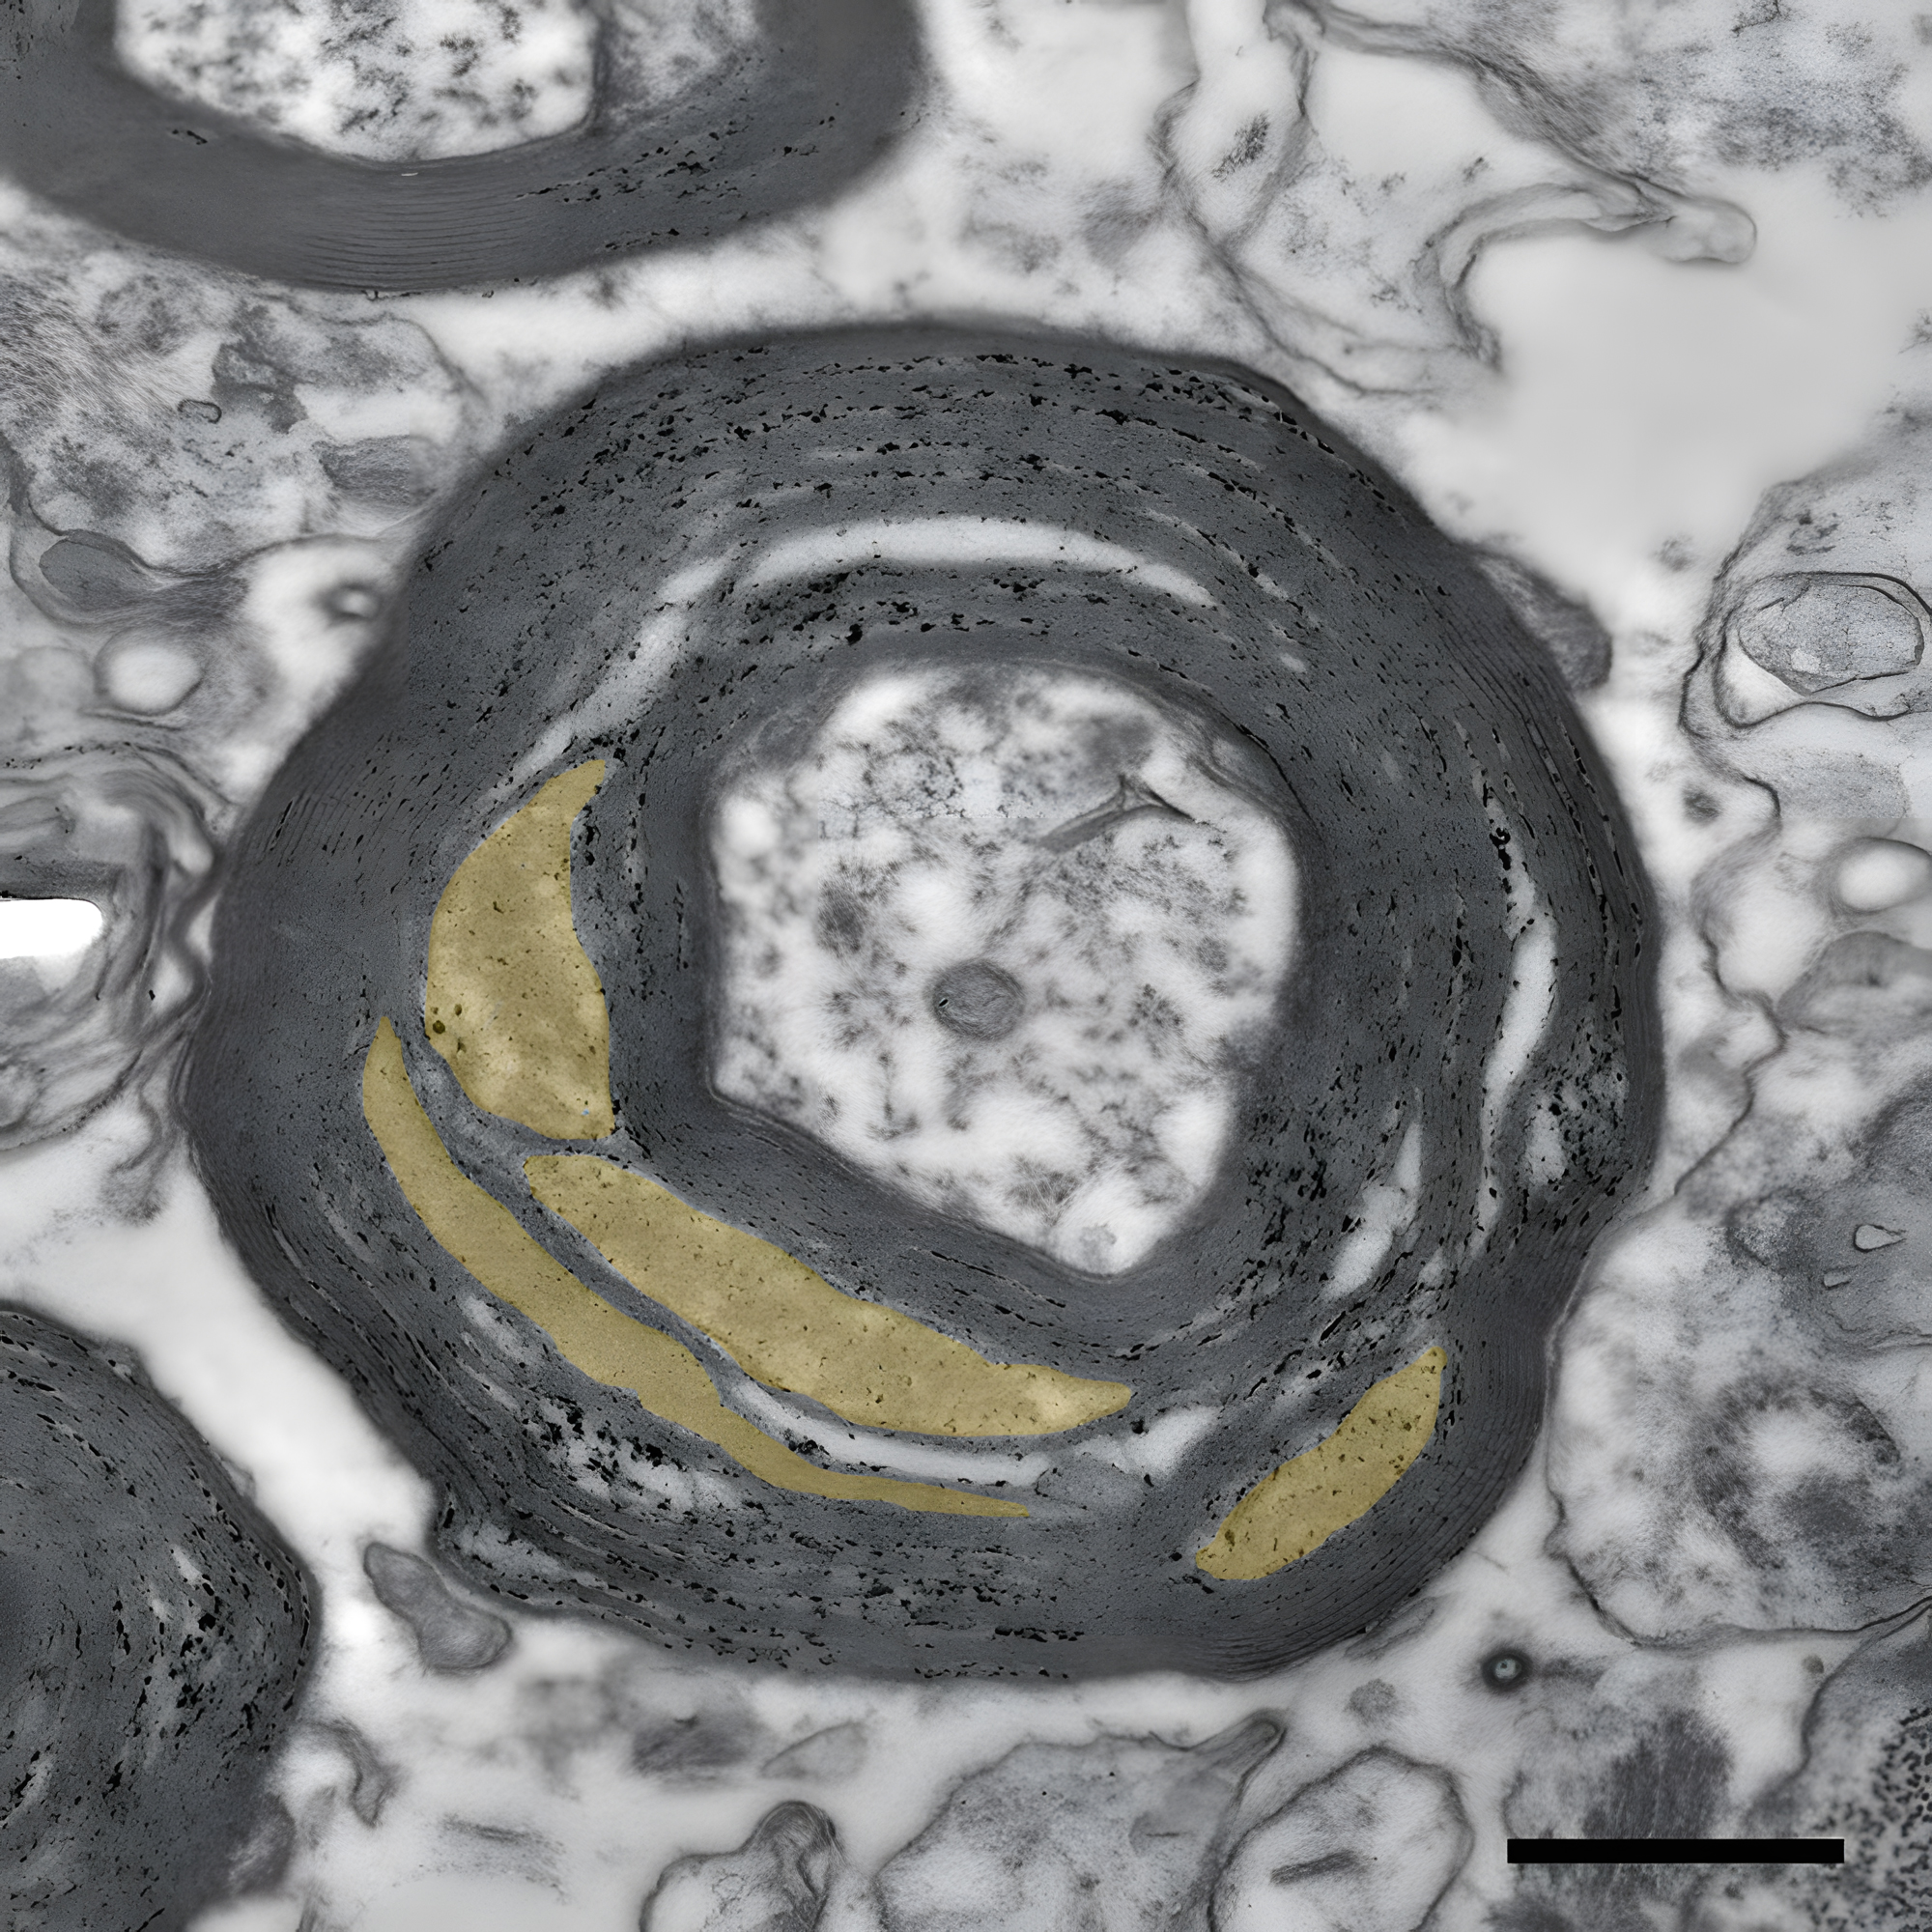

Morgens sieben Uhr, der Wecker klingelt – Augen aufschlagen, Beine aus dem Bett schwingen, auf der Arbeit einen Vortrag halten, abends ein Tennismatch spielen. All dies ermöglichen uns Milliarden von Nervenzellen, die die graue Substanz in unserem Gehirn bilden. Sie sind millionenfach miteinander verschaltet durch tiefer im Gehirn verlaufende Nervenfasern, Axone genannt. Viele dieser Axone sind von einem zellulären „Isolierband“ umwickelt. Die Isolierschicht besteht aus Myelin, einer fettreichen Substanz, die Axone in bis zu 150 Schichten umhüllt. Axone und Myelin bilden zusammen die sogenannte weiße Substanz. In regelmäßigen Abständen weisen die Myelinscheiden eine kleine Lücke auf, die als Ranvierscher Schnürring bezeichnet werden. Wird ein Signal mittels eines elektrischen Nervenimpulses von einer Zelle zur nächsten übermittelt, springt dieser regelrecht von einem Schnürring zum nächsten. Dies macht die Kommunikation an myelinisierten Axonen 100 mal schneller.

Wie das Forschungsteam zeigen konnten, sind in der normal aussehenden weißen Substanz von MS-Erkrankten die Myelinscheiden auffällig verändert und das Myelin weniger kompakt. Auch sind die Ranvierschen Schnürringe desorganisiert. Neben diesen Strukturveränderungen fanden die Forschenden in dem scheinbar normalen Gewebe auch zelluläre Marker für eine Entzündung: T-Lymphozyten und aktivierte Immunzellen des Gehirns, Mikrogliazellen genannt. Nicht zuletzt war auch die Dichte der Mitochondrien – die Kraftwerke der Zelle – in den Fortsätzen von Nervenzellen auffällig erhöht, was nahelegt, dass die Kommunikation zwischen Nervenzellen mehr Energie erfordert als bei gesunden Menschen. Aletta van den Bosch aus dem niederländischen Team erklärt dazu: „Mitochondrien produzieren allerdings nicht nur lebenswichtige Energie, sondern auch viele Nebenprodukte wie Sauerstoffradikale. Wir vermuten, dass diese den Myelinabbau verstärken könnten.“

„Wir sehen sehr deutlich, dass bei MS ultrastrukturelle Veränderungen der weißen Substanz mit chronischen Entzündungen im Gehirn zusammenhängen. Beide krankhaften Auffälligkeiten könnten zum Fortschreiten der Krankheit beitragen. Dass sich die Ultrastruktur des Myelins nun in einer solchen Qualität für Untersuchungen im Elektronenmikroskop erhalten lässt, wird hoffentlich weitere neue Einsichten ermöglichen“, so Möbius.